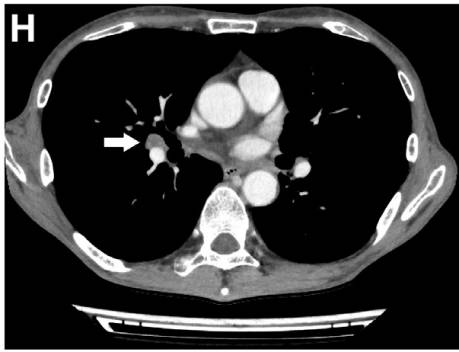

腹部CT增强扫描显示,纵膈淋巴结及肺门淋巴结肿大(图G、H)。